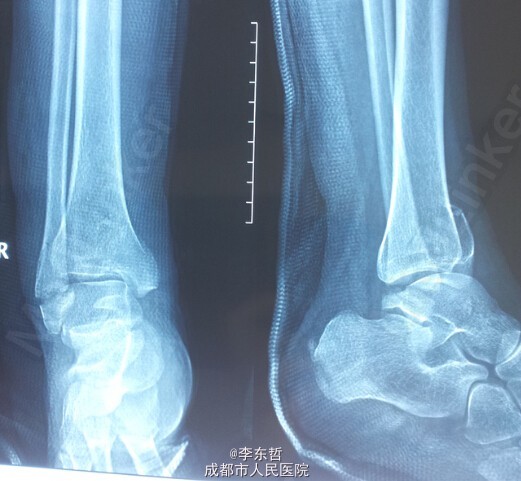

左下肢胫腓骨骨折伴右下肢内外踝骨折一例

患者,女,26岁,外伤致左下肢胫腓骨骨折、右下肢内外踝骨折,入院后右侧临时石膏固定、左侧骨骨牵引10天后,双侧同时手术,左侧胫骨采用MIPPO技术内侧钢板固定。